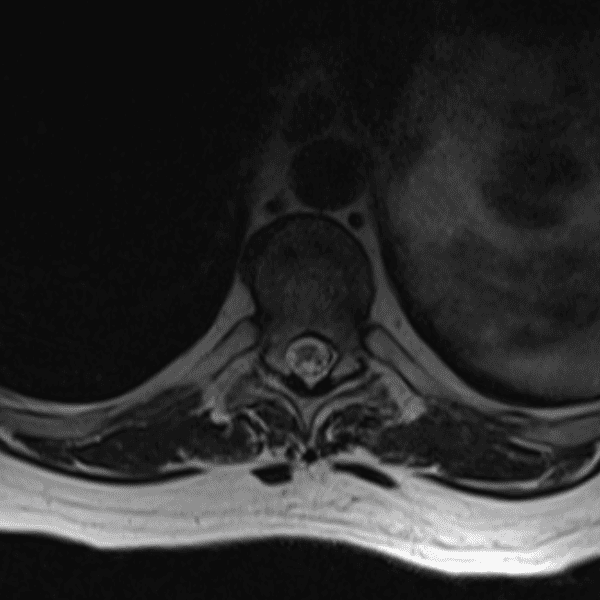

Simulates call by including subtle or difficult cases and some normals.

35 cases